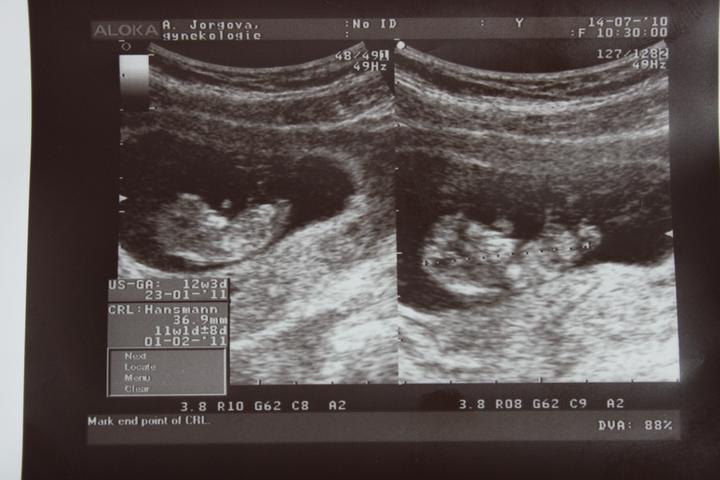

tak dnešní kontrola dopadla výborně, odpovídáme 11+1tt 🙂